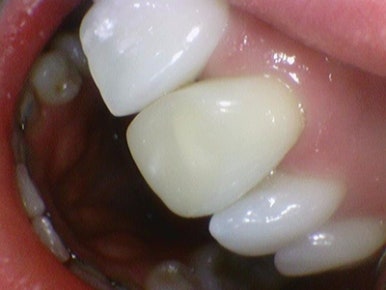

치료 전, 앞니 1개 크라운 치료 후

환자분은 20대 외국인 환자분으로

이미 만8살 때 사고로 앞니 하나에 신경치료를 하였고, 그 후 변색이 되어 15년 넘게 변색된 대문니 앞니 하나를 가진 앞니빼고는 완벽한 외국인 여자분이었습니다.

이렇게 하나만 누렇게 딱 보이는 치아가 있으니 웃지도 못하고 어릴 때, 사춘기 동안 얼마나 힘드셨을까요

앞니 1개 크라운치료 후

치아를 깎고 임시치아를 끼고 가시고, 다음에 만들어온 크라운을 붙이러 오셨는데요

앞니 1개 크라운 치료 후